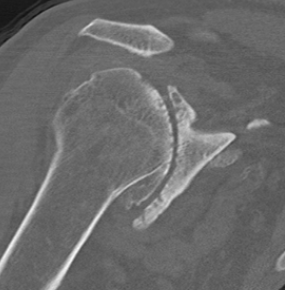

Xray

Typical changes of RA

- regional osteopenia

- marginal erosions and cysts

- humeral head erosions

- medial migration / protrusio

DDx

- septic arthritis

- gout / pseudogout

- Milwaukee shoulder (calcium hydroxyapatite crystals)

- rotator cuff arthropathy

- OA (beard osteophytes)